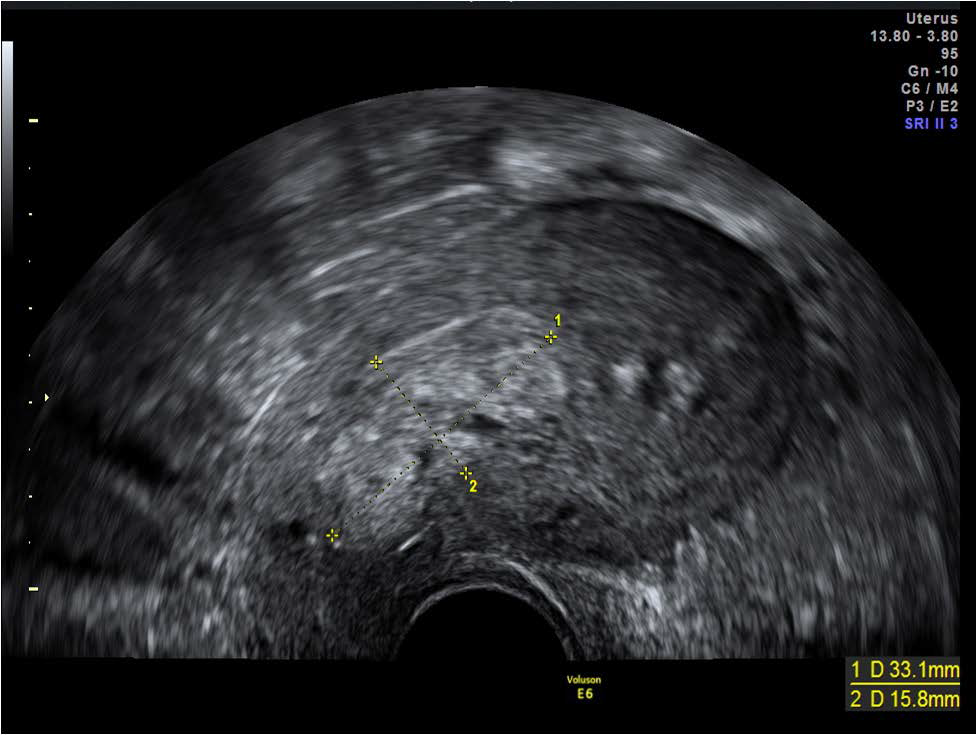

Figure 7: Echogenic mass seen within the lower uterine segment in the sagittal plane on transvaginal scan performed in a symptomatic patient 8 weeks post vaginal delivery.

figure 7